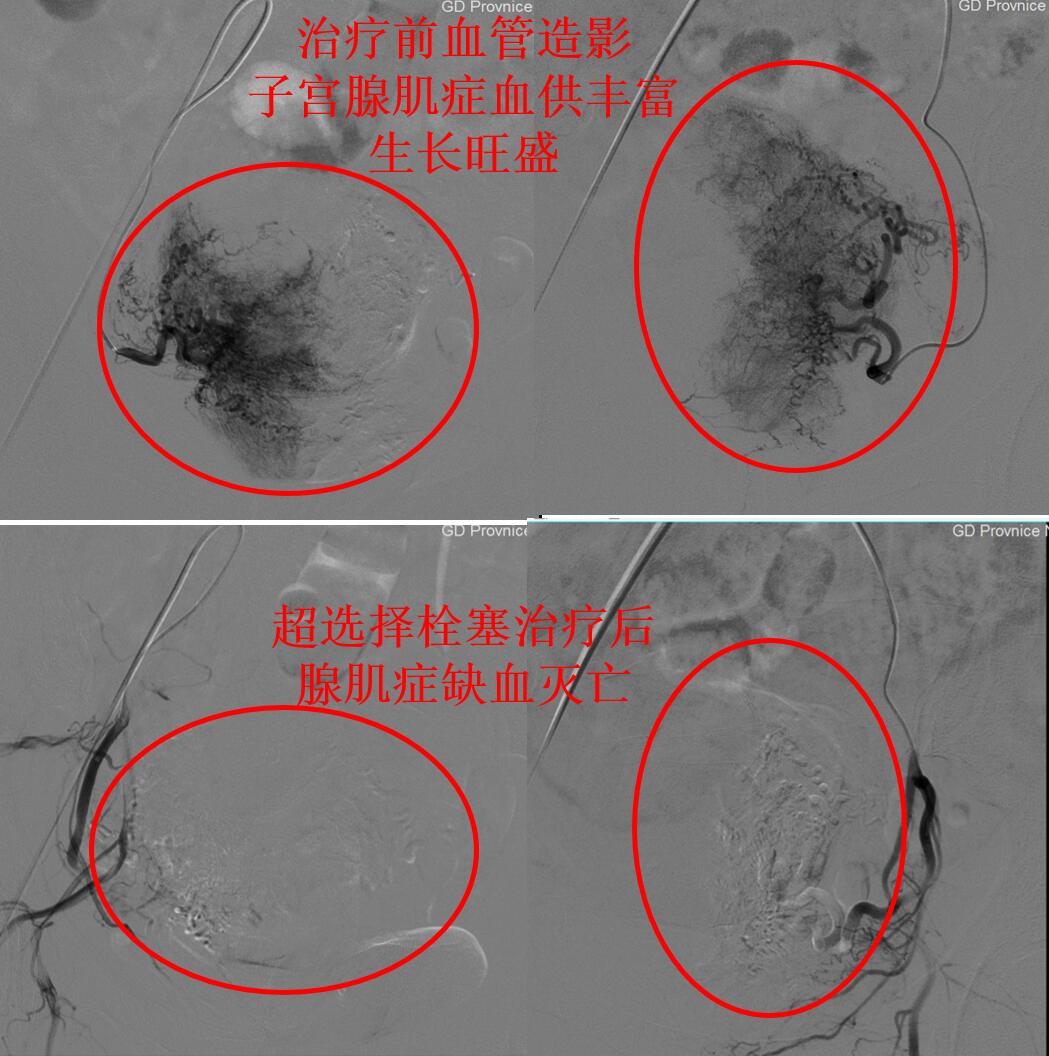

上图为介入微创超选择栓塞治疗腺肌症的前后对比

介入微创栓塞治疗后第2天,张女士即可下床步行活动。治疗后1个月张女士来例假,痛经明显好转,仅有轻微隐痛;第2次例假痛经完全消失。3个月后复查超声造影显示:子宫腺肌症灭亡,子宫缩小(如下图)。